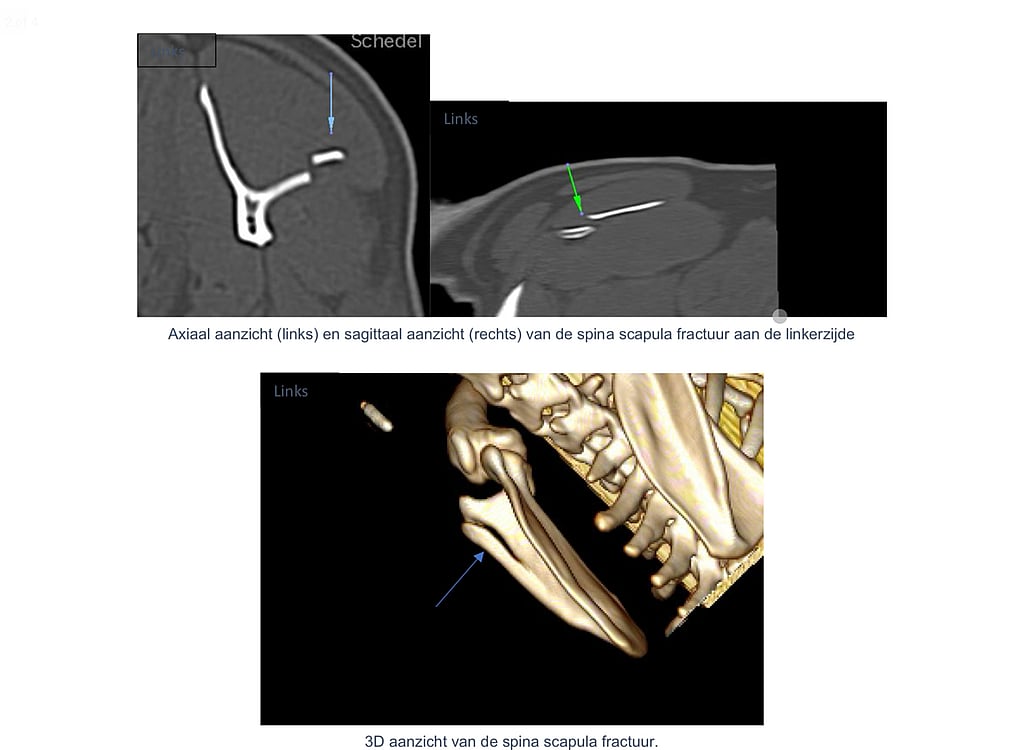

Dorsale en coronale CT-beelden tonen een overlangse partiële fractuur van de spina scapula, zonder dislocatie en met intacte caudale aanhechting.